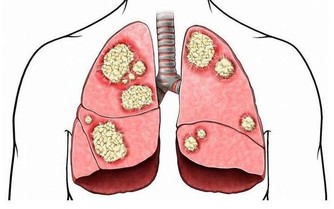

肝臟是最容易生病的器官

由於肝臟最忙最累,又由於肝臟面對有毒有害物質的侵襲,再由於肝髒又任勞任怨,所以肝臟最容易受到傷害,患病最多,也最難治,諸如,甲肝、乙肝、丙肝、黃疸型等等,酒精肝、脂肪肝、肝硬化等等。了解了肝臟的特點,我們就能應該善待和保護自己的肝臟。從醫藥學研究和臨床時間來看,目前大多數肝病是很難單純依靠藥物來治好的。能夠有效激活人體的免疫系統,調節肝臟代謝,清除體內毒素,幫助受損的肝細胞修復,有利於肝細胞生成。